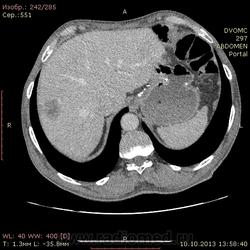

69 лет. КТ контроль от августа. Посте очередного курса химии. Начало истории здесь http://www.radiomed.ru/cases/kt-bryushnoi-polosti-adenokartsinoma-zheludka-sostoyanie-posle-rezektsii-zheludka-mts-v-pechen

Сегодня выглядит так. DICOM здесь http://files.mail.ru/2A18DCE6A6AA4546B51713D2F9C9E91A

На мой взгляд метастазов новых нет, но старые увеличились и один из пораженных л\у также увеличился.